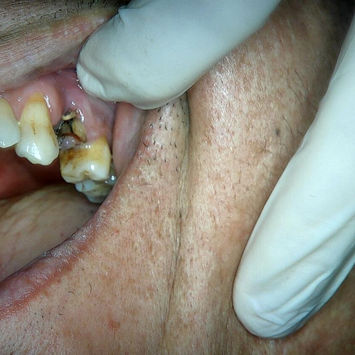

Clinical Findings

Retained roots at #24 with infection.

Buccal bone deficiency identified.

Pre-operative CBCT and photographs taken for assessment.